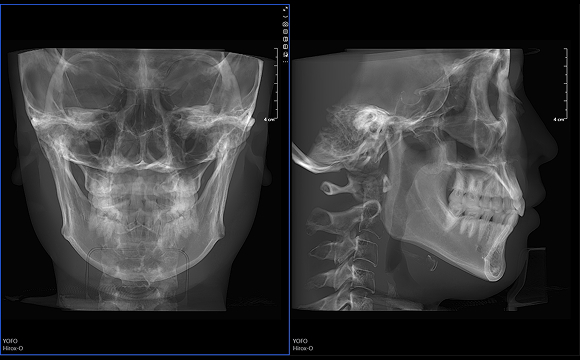

• 3D 正側位

3D 正側位

只需一次單圈掃描即可獲得CT、數字全景和3D正/側位影像,

并能同時生成3D TMJ視圖 提高診療效率,避免過度檢查,減少患者所受的輻射